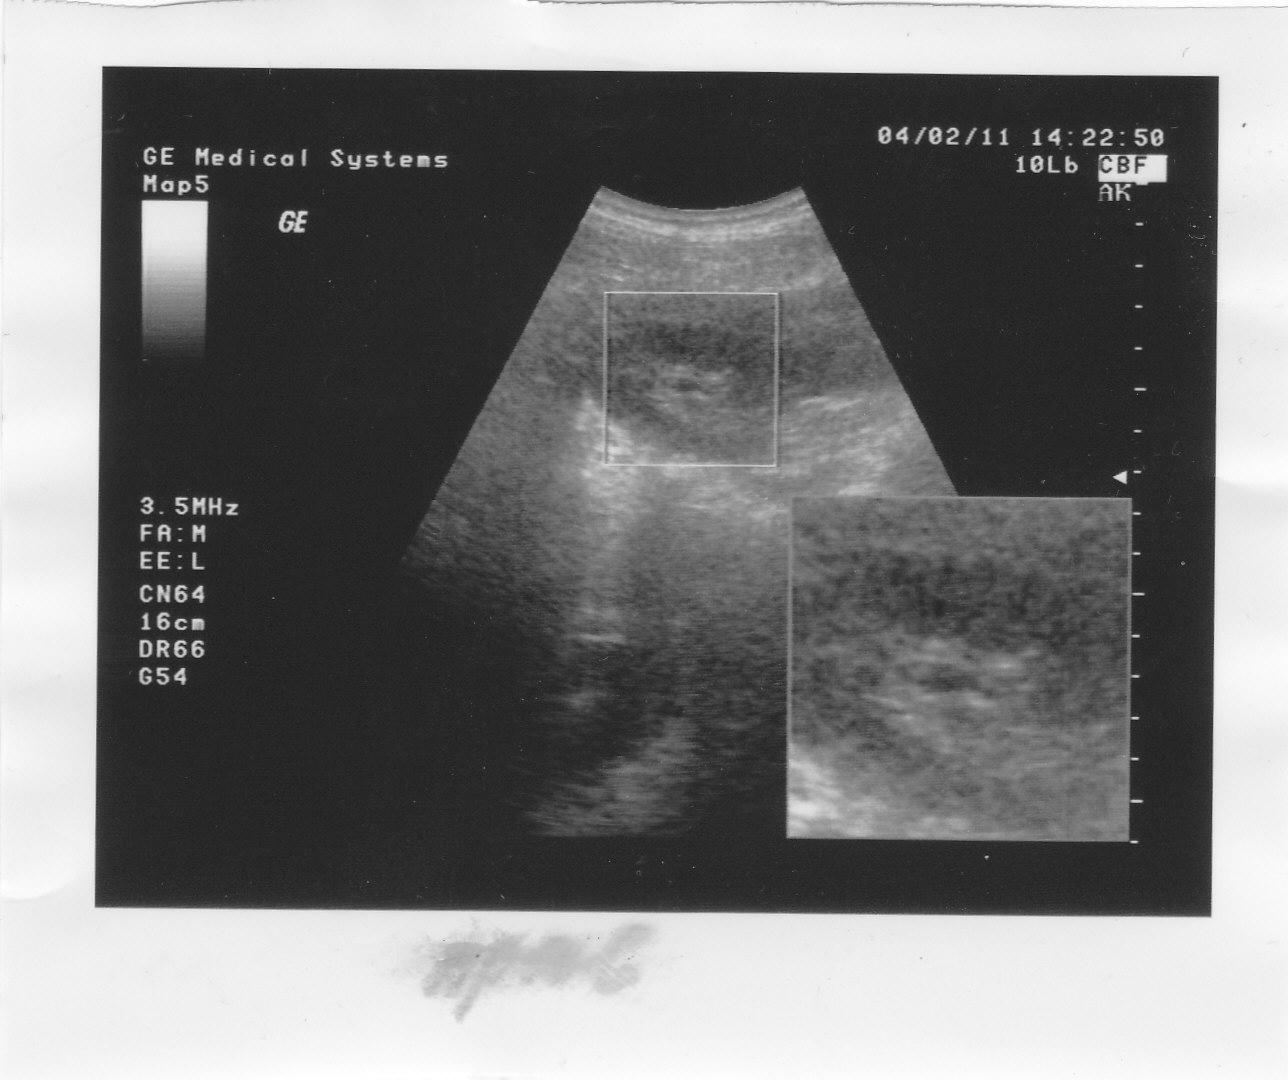

А в 2010 году на снимке видно что то в правой, не оперированой почке.Анализы все в норме.

В 2011 году сделаны снимки обеих почек на консультацию к урологу.Анализы все в норме.

Отправляю снимки УЗИ.